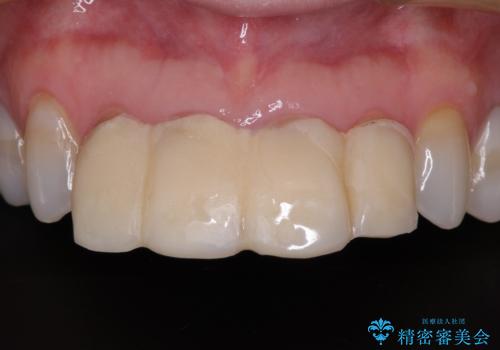

銀歯の下のむし歯については、優先度の高い方からセラミッククラウンなどで治療していくこととしました。

治療開始時は右上奥歯と前歯のみが気になっていたのですが、その後下顎左右の奥歯に強い痛みや銀歯の脱離などが頻発し、問題のあるところは全て治療を行うこととしました。